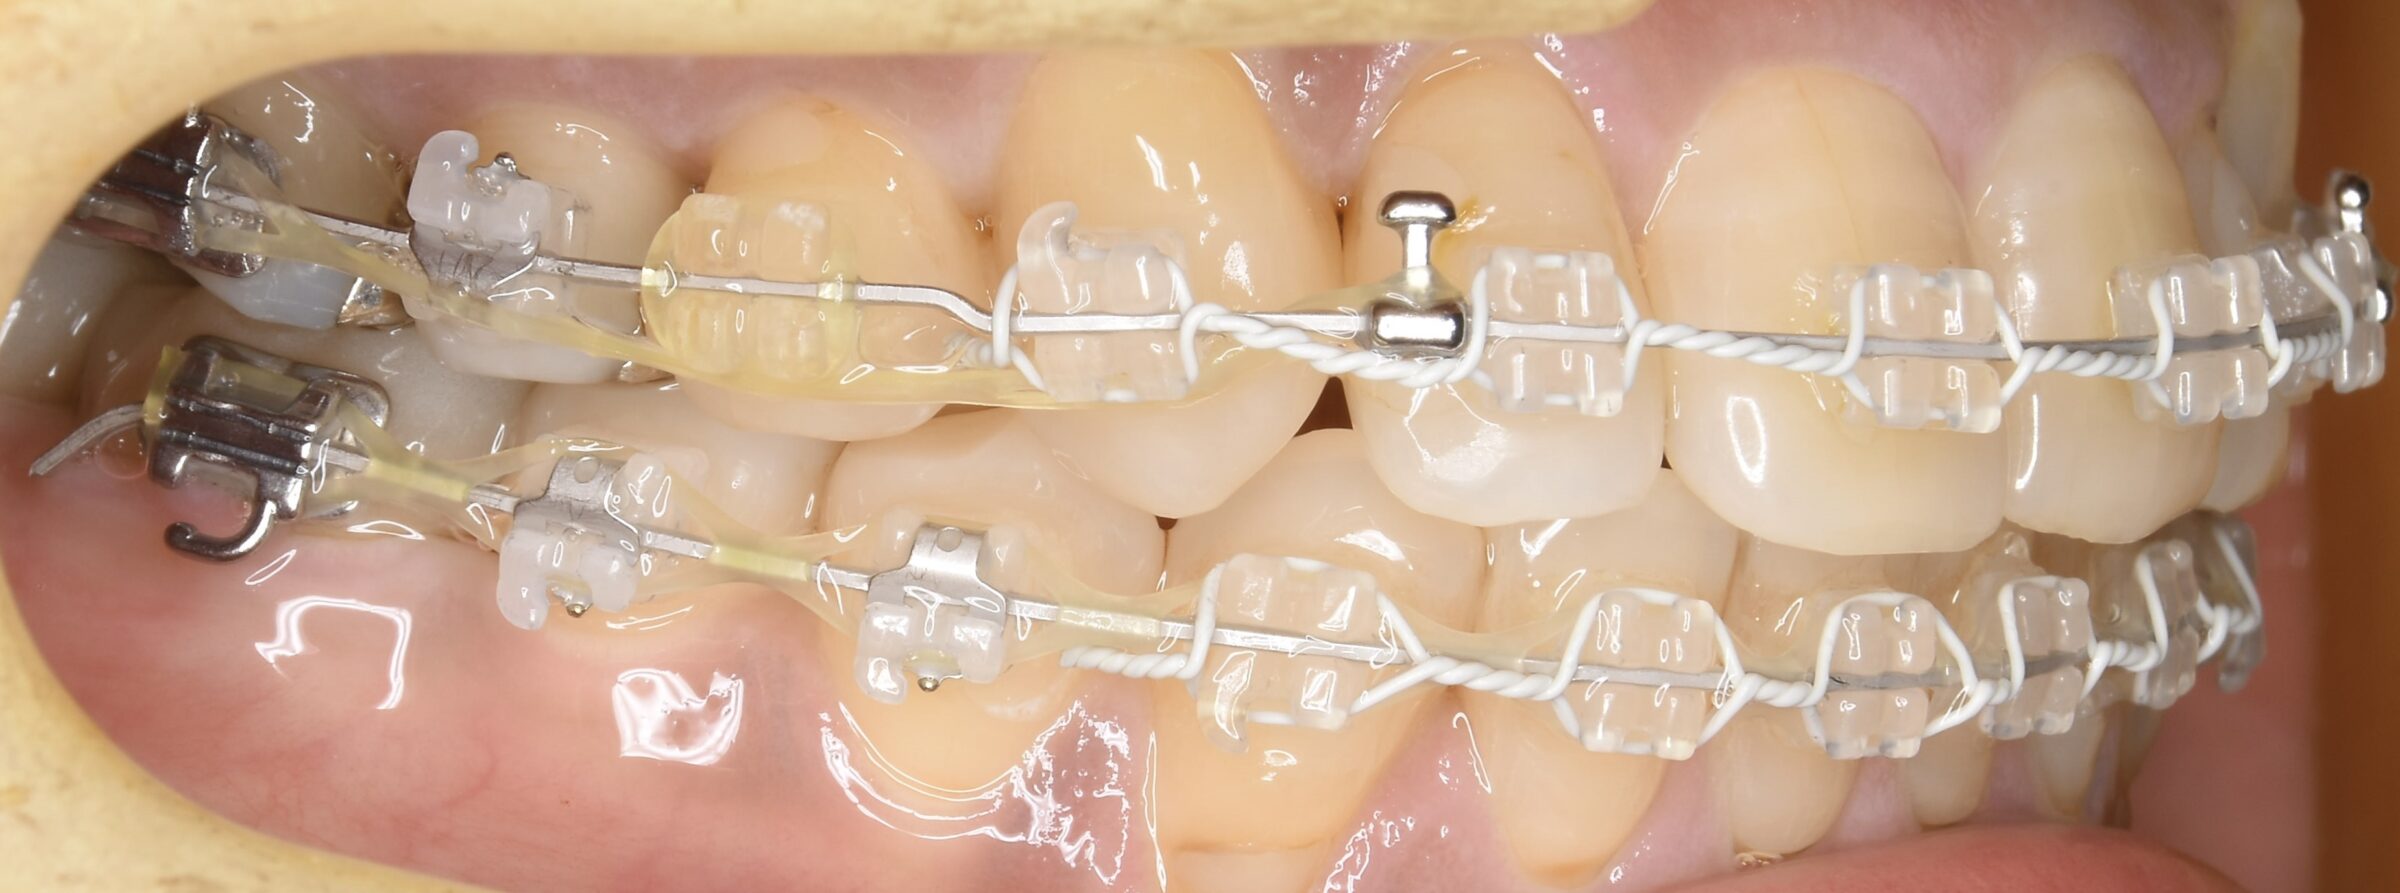

治療中の口腔内写真

①歯の位置が不正な場合は、矯正治療で歯を動かすことで削ることを避ける。

②元々、銀歯が入っているような歯も、矯正治療で適正な位置に動かすことで、むし歯と歯周病の再発リスクを下げる。

③インプラントと隣接する歯、インプラントと噛み合う歯、を矯正治療で適正な位置に動かすことで、インプラントが長持ちする。

④無理な角度や方向性の被せ物(セラミック修復)を避けることで、セラミック歯が長持ちする。